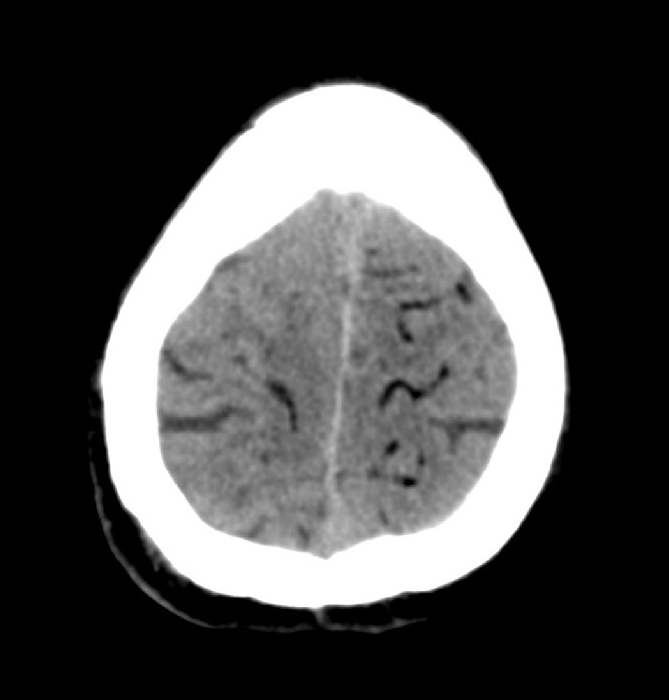

sealing of needle track 是预防空气栓塞的措施。57岁上肺空洞病变。临床结核检查阴性。内镜检查既没显示结核,也没发现肿瘤。病灶对侧侧卧位,CT引导下17/18G 同轴活检,不同方向取样4次。活检期间患者咳嗽一次。术后CT扫描,未发现气胸,出血并发症。患者恢复仰卧位,移位到运转平车上。患者突然昏迷,立即进行头颅CT平扫显示脑气栓。立即气管插管和正压通气,Trendelenburg 位。尽可能长的在CT床上胸部对照CT扫描,除外左心或升主动脉气栓。

后患者去高压氧治疗,5天后CT扫描正常,没有脑缺血表现。患者没有任何主诉。但神经科检查,仍存在右侧轻度锥体束综合征。肺活检结果为炎症,没有发现肿瘤。18天后患者出院。 总结这个病例,至少可以指出四个由CT引导的肺活检引起空气栓塞的危险因素: 1. 空洞性病变, 2. 手术过程中咳嗽 4. 病变位置高于左心房水平 4. 以传统方式使用同轴针,即多次打开外部套管与大气接触。 文献上关于空气栓塞的潜在危险总结如下 【Mansour 2005;Rott 2014】